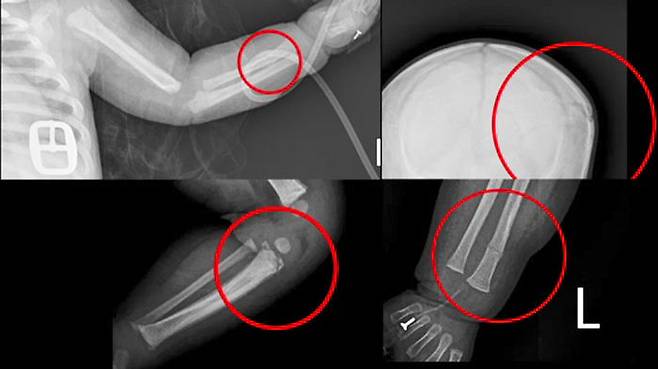

다급하게 병원에 도착한 생후 3개월 아기에게서는 무려 16가지 문제가 발견됐습니다.

머리뼈와 갈비뼈, 어깨뼈 등 모두 11곳에 골절이 있었고 뇌출혈까지 일어난 상태였습니다.

주치의는 뼈마다 부러진 시기가 다르고 심각한 영양실조로 볼 때 장기간 학대가 이뤄졌을 것으로 추정했습니다.

[배기수/아주대병원 소아청소년과 교수 : 선천성으로 뼈가 약해서 부러지고 그런 말을 들었는데 저는 소아정형외과 전문가고 이렇게 본 결과 그건 아니다. 뼈 자체의 질환은 없는 거다, 이렇게 판단이 됐습니다.]